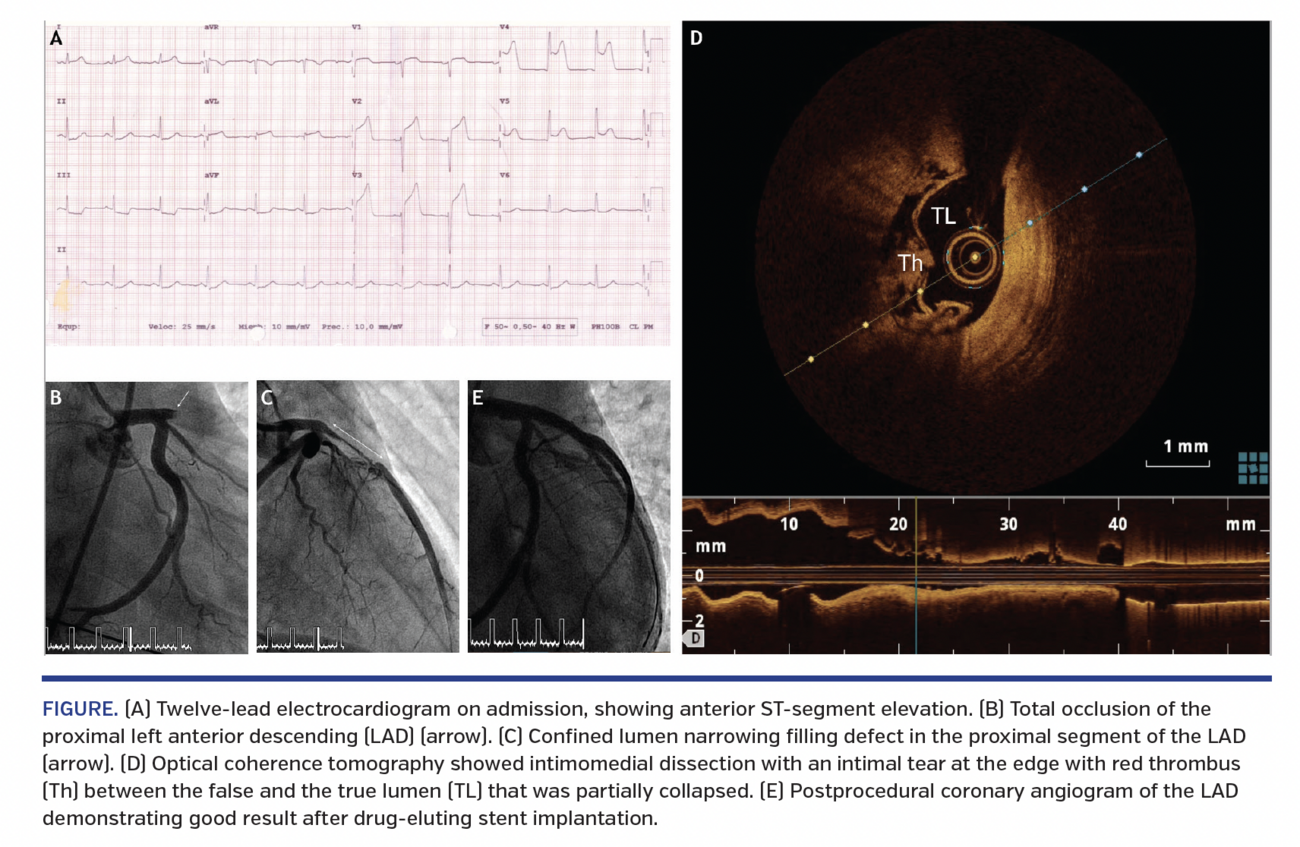

We describe a 26-year-old-man with no previous medical history, who suddenly collapsed. He was a cocaine user and had inhaled 2.5 g cocaine about 2 hours before the episode, which was confirmed with positive urine toxicology. Emergency services started on-site cardiopulmonary resuscitation shortly thereafter. A 12-lead electrocardiogram showed anterior ST-segment elevation (Figure 1A). After stabilization, he was transferred for primary angioplasty. Coronary angiography showed a total occlusion of the proximal left anterior descending (LAD) coronary artery (Figure 1B). We gently advanced a guidewire into the LAD without recovery of distal flow. As we suspected large thrombus burden, we performed thrombus aspiration. Although no macroscopic thrombus was retrieved, TIMI 2 flow was achieved. A confined lumen narrowing filling defect in the proximal segment of the LAD was then observed (Figure 1C). This coronary narrowing remained similar after intracoronary nitroglycerin administration. Optical coherence tomography (OCT) showed an intimomedial dissection with an intimal tear at the edge with red thrombus between the false lumen and true lumen that was partially collapsed (Figure 1D). A drug-eluting stent was then implanted with excellent result (Figure 1E).

There are many underlying mechanisms for CAMI, and the culprit has to be elucidated for appropriate therapeutic management. OCT provides unique insights when angiography alone has limited diagnostic value. OCT also aids in the decision between conservative management and revascularization strategy and guides coronary interventions.